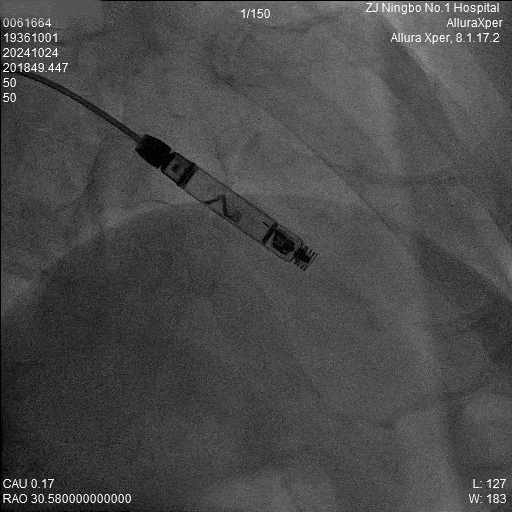

2.回撤保护套筒,激活新型螺旋主动无导线起搏器备用起搏:在无导线进入人体血管后形成起搏回路,以低能耗的传导式通信方式进行激活(1-2分钟)。

患者二的植入情况如下:

RAO 30猪尾导管造影